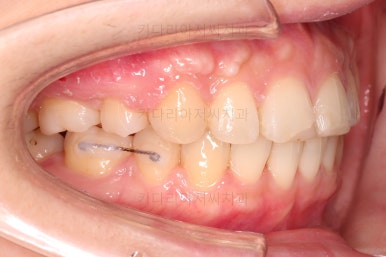

오늘 부산연산동교정치과 키다리아저씨치과에서 소개해 드릴 환자분은 입이 돌출이 되었고 교합이 맞지 않아(과개교합 및 2급 부정교합) 교정치료를 원하셨던 환자분입니다.

치아, 특히 윗니가 앞으로 튀어나와 웃거나 말할 때 강조되어 보이고 돌출되어 보여요.

당연히 치아가 나와있어서 입매도 튀어나와 보이죠.

거기다 입을 다물기가 힘들고 어색해서 입가~턱끝까지 항상 힘이 강하게 들어가 있어요.

이러한 입술의 부자연스러운 모습은 치열을 뒤로 넣어줘야 개선이 가능해요.

윗니가 전반적으로 아랫니보다 앞에 나와 있어서 2급 부정교합에 윗니만 튀어나온 양상이고 이 때문에 윗니 앞니가 다치고 부러졌따가 떼운 흔적이 보이네요.

옆라인만 비교해보면요.

입매가 거의 변하지 않는 타입이세요.

교정장치 때문에 입이 많이 나올지, 안나올지는 사람마다 매우 달라서 말그대로 붙여봐야 아는 경우가 많습니다.

치아를 뽑은 위치, 당겨야 할 정도가 달라 미니스크류를 몇 개 사용했어요.

미니스크류는 앞뒤조절, 높낮이 조절, 각도 조절, 안밖의 위치조절 등 난이도 높은 치료를 가능하게 해준답니다.

점점 치열이 가지런하게 되면서 발치한 자리도 조금씩 없어져가네요.

남는 자리는 입을 뒤로 넣는데 이용됩니다.